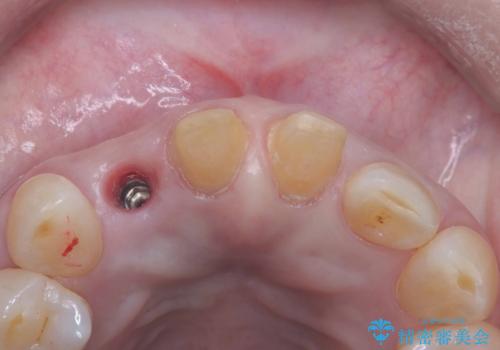

インプラント治療は、低侵襲で短期間に行える「抜歯即時インプラント治療」を選択しました。

この方法は、抜歯したその日にインプラントを埋入し、手術が1回で済むのが大きな特徴です。

治療期間も短く、抜歯からわずか3か月でオールセラミッククラウンを装着することができます。

また、オペ当日には仮歯まで装着するため、見た目を気にせず普段通りの生活を送ることができます。